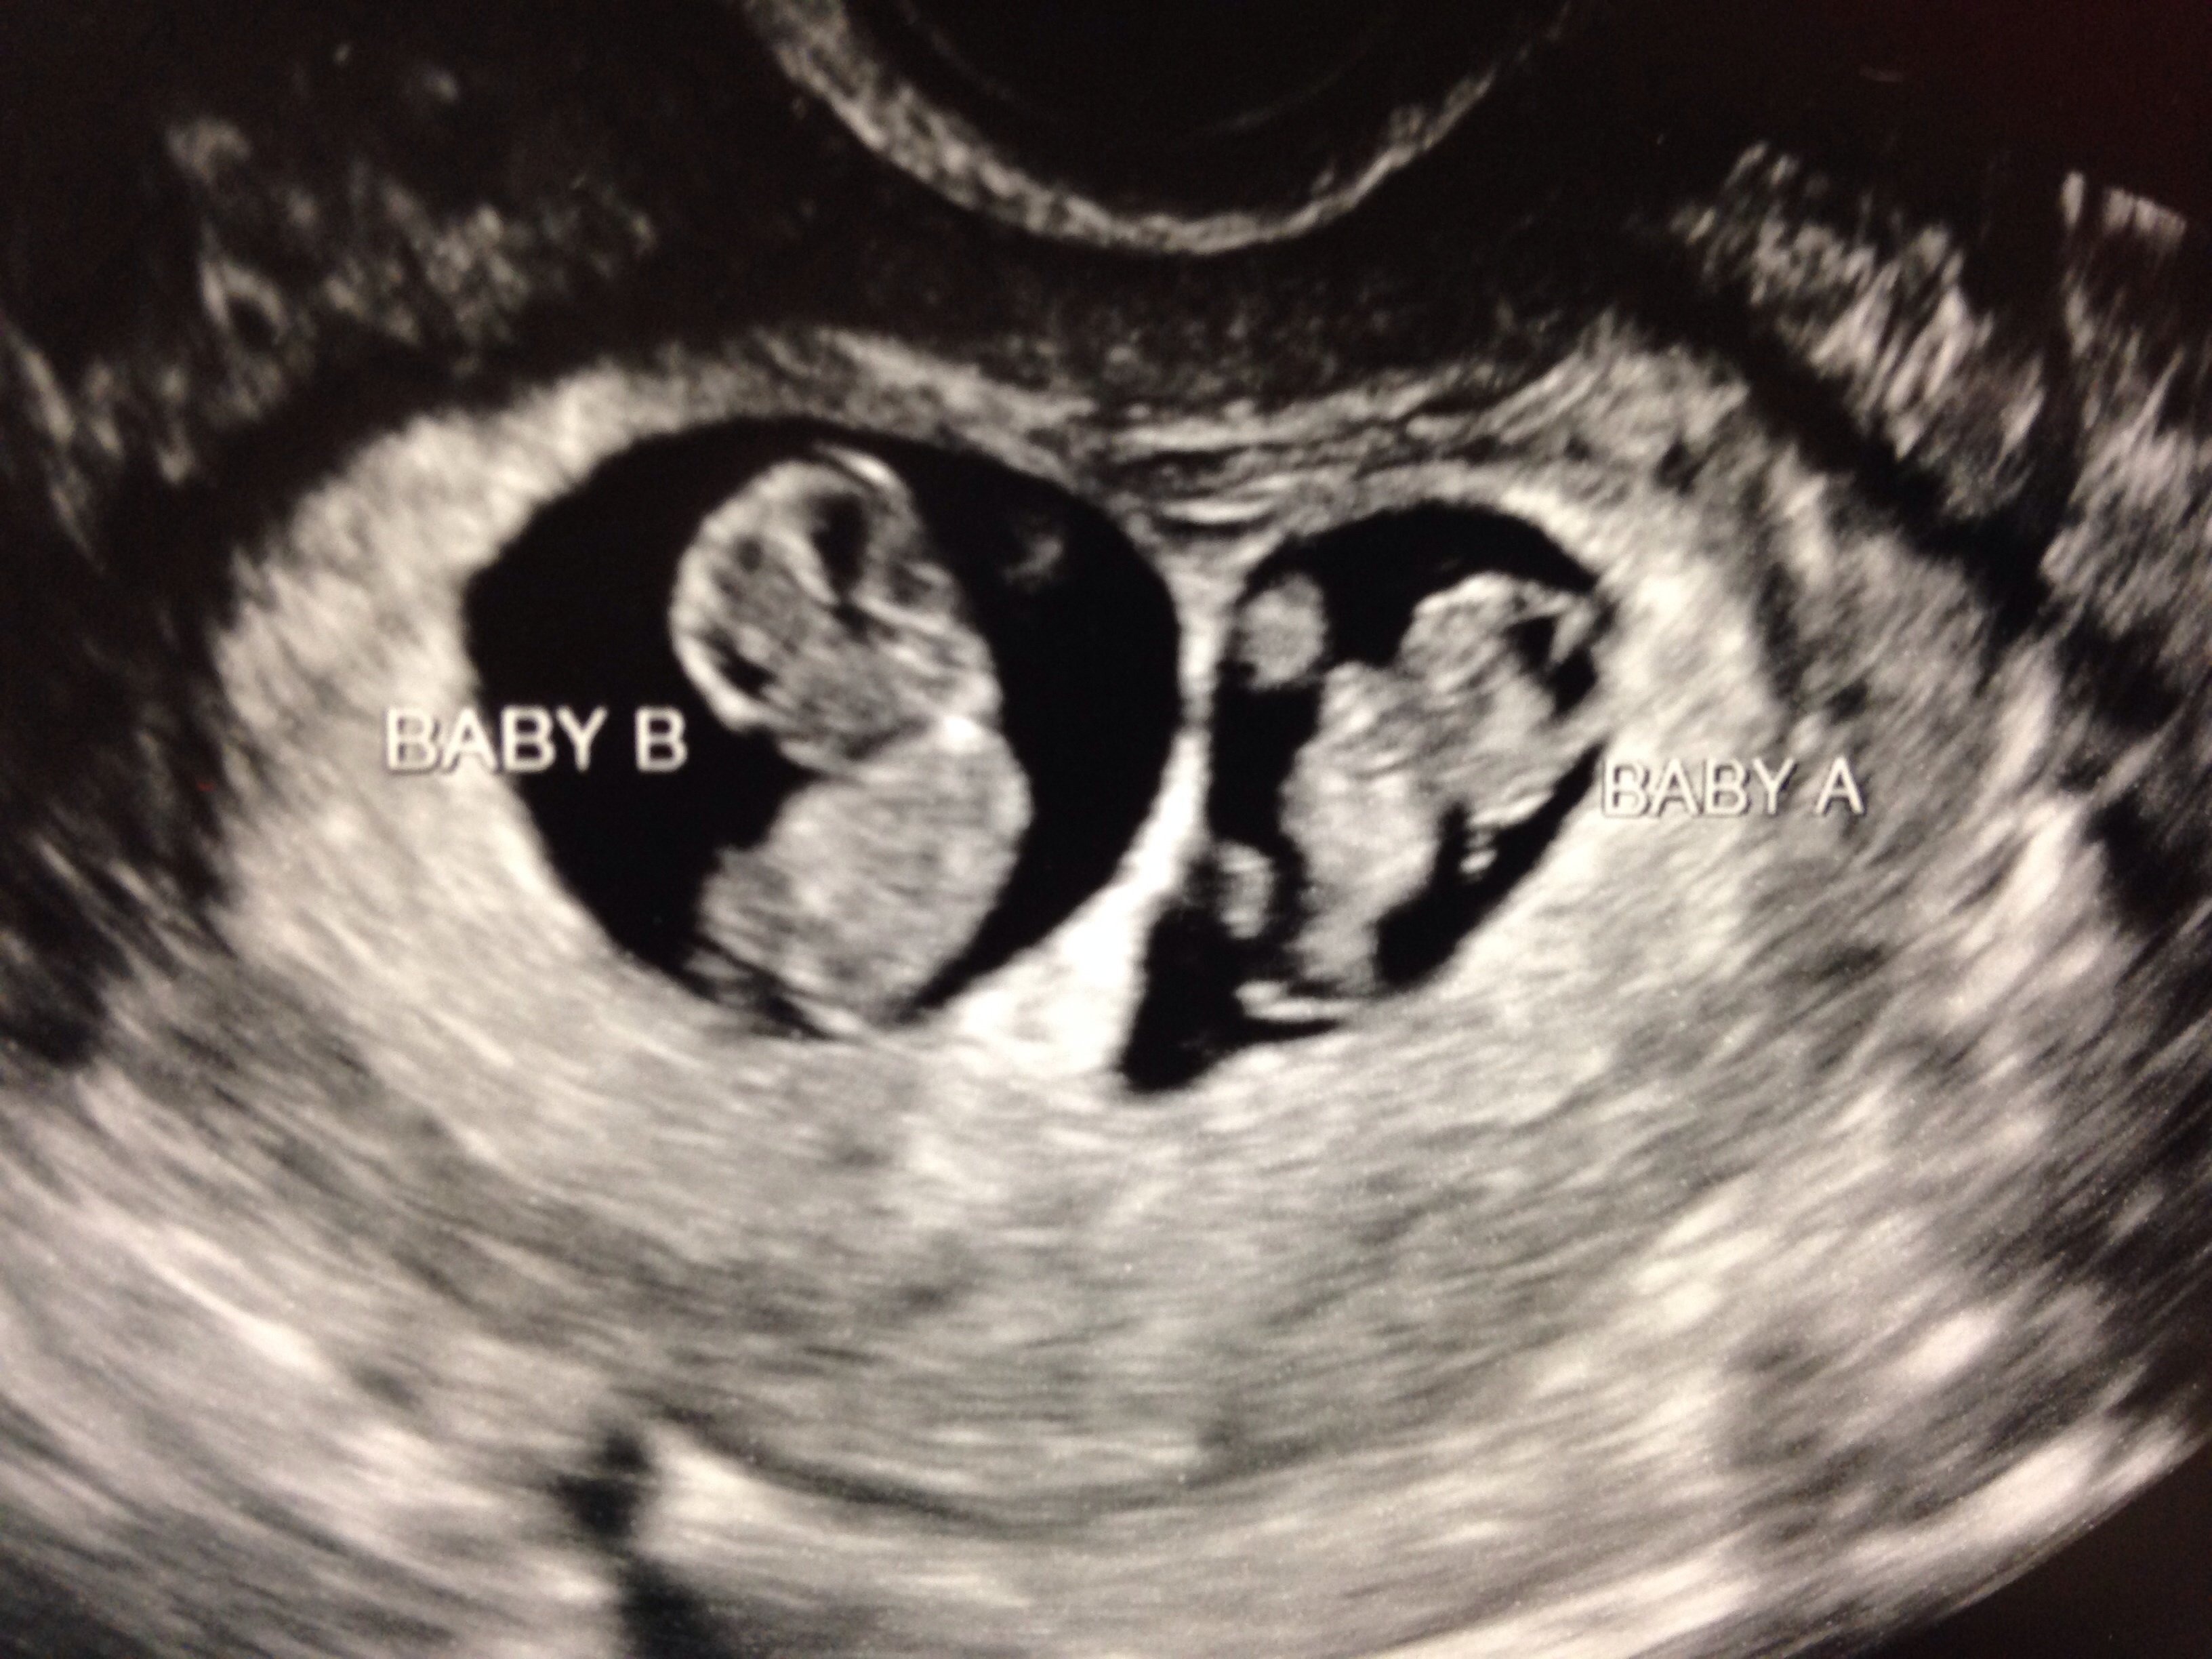

9w6d here are my little guys! I have not been on in two days and it just breaks my heart seeing all the loss! With in 3days of finding out i was finally pregnant, two of my girlfriends had ectopic pregnancies that ended in loss of a tube. So sad and just makes the reality of a loss more real. Edit....Not sure why my pic is not showing.

TTC 31\2 years 20 medicated cycles of some kind, 8 failed IUIs (every med combo possible) 5/14/14 IVF # 1, 6dp5dt BFP, Betas 8dp5dt- 67, 14dp -670, 17dp -1761, 20dp-4858, 27dp-28,800 6/11/14 6w3d Twins!!! - EDD Feb 1st

F15 January Siggy Challenge: What I'm Looking Forward to After the Babies Arrive Bringing them both home...UPDATE...The girls are home!!! 1/7/15 after 20 days in the NICU!

20 medicated cycles of some kind, 8 failed IUIs (every med combo possible)

5/14/14 IVF # 1, 6dp5dt BFP,

Betas 8dp5dt- 67, 14dp -670, 17dp -1761, 20dp-4858, 27dp-28,800

6/11/14 6w3d Twins!!! - EDD Feb 1st

Bringing them both home...UPDATE...The girls are home!!! 1/7/15 after 20 days in the NICU!